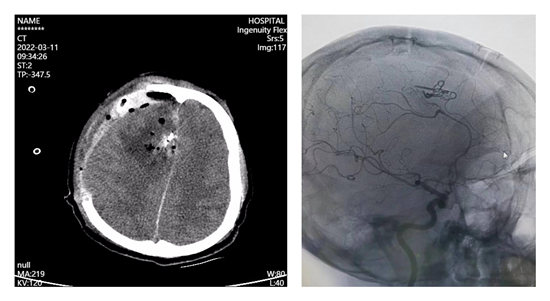

术后复查颅脑CT提示血肿清除干净及动脉瘤夹闭及复查脑血管造影提示动脉瘤基本夹闭,无残留,载瘤血管通畅,无狭窄